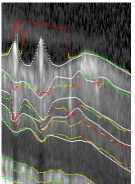

The average segmentation error of 2.46μm2.46𝜇𝑚2.46\,\mu m is significantly smaller than for circular scans, as well as the standard deviation of 0.22μm0.22𝜇𝑚0.22\,\mu m. Reasons are smoother boundary shapes and less severe texture artifacts caused by e.g. blood vessels. Representative for the average segmentation performance, Fig. 14 shows B-scans of the same volume from four different regions, with an error of 2.53μm2.53𝜇𝑚2.53\,\mu m averaged over the all scans in the volume.

Refer to caption

(a)

(b)

(c)

(d)

(e)

(f)

(g)

(h)

Figure 14: Four segmented B-Scans from regions 2, 6, 9 and 11 of the same volume (Eunsgn=2.53μmsubscript𝐸unsgn2.53𝜇𝑚E_{\mathrm{unsgn}}=2.53\,\mu m).